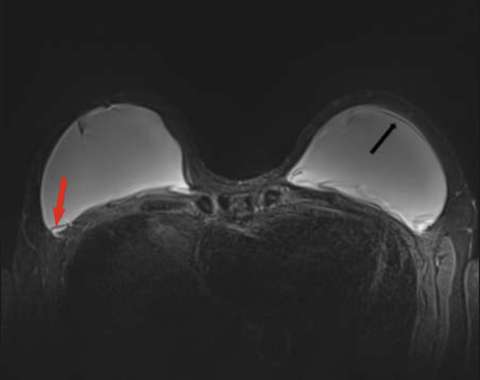

Extracapsular ruptures appear as free silicone material extending beyond the fibrous capsule into the adjacent tissues on T2-weighted and silicone-sensitive sequences3 (Figure 6).